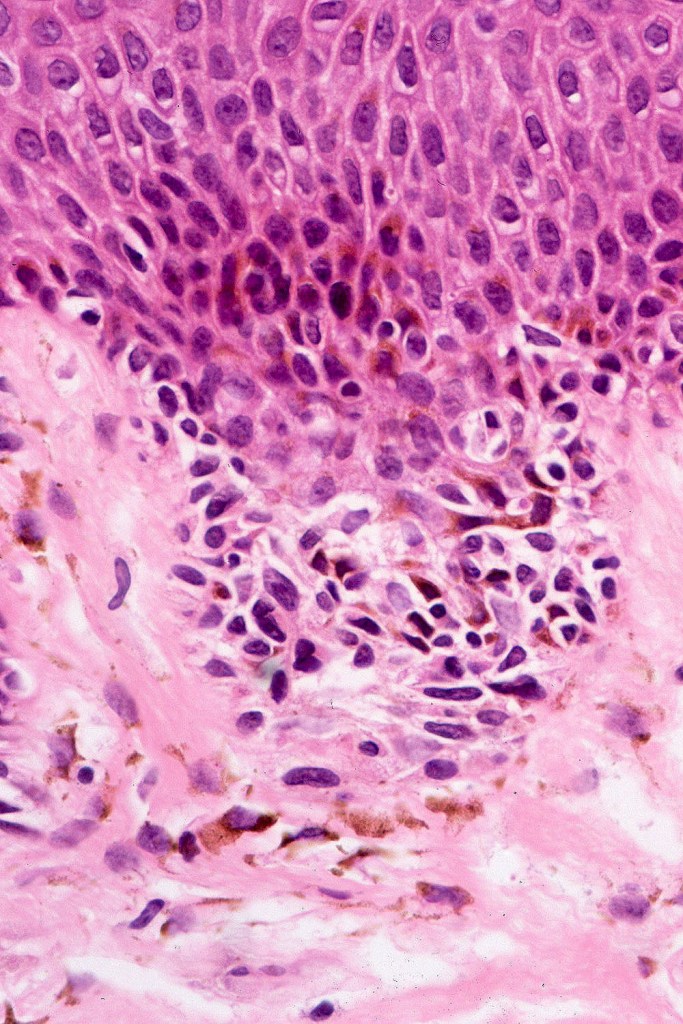

•Cytological atypia- mild, moderate & severe (or more recently, low & high grade (WHO). The problem with the new WHO classification is that mildly dysplastic nevi are now included with the banal nevus category and moderate is low grade and severe is high grade. In all likelyhood, most pathologists will include mild & moderate atypia in the low grade category.

•Variation in the degree of atypia within any one lesion is commonly present

Dysplastic nevus in the majority of cases is instantly recognizable, often at low power. The most important differential diagnosis is obviously melanoma. In junctional lesions, widespread/uniform high grade atypia, frequent mitoses and Pagetoid spread are indicative of in situ melanoma. In compound lesions, dermal nests larger than junctional ones, expansile dermal nests, severe atypia and mitotic activity indicate the presence of melanoma

Dysplastic nevus with early melanoma